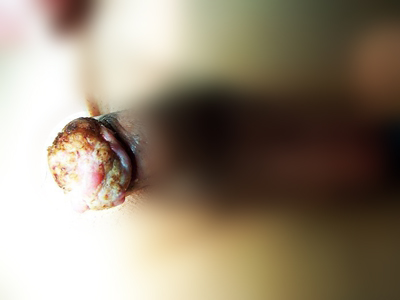

阴茎癌多见于40-60岁有包茎或包皮过长的人群。若包皮可上翻显露阴茎头,早期可有类丘疹、疣状红斑或经久不愈的溃疡等病变。若包茎或包皮过紧,不能显露阴茎头,可有包皮内刺痒、灼痛等症状,或触及包皮内硬块,并有血性或脓性分泌物流出。

随着病变发展,疼痛加剧,肿瘤突出包皮口或穿破包皮,晚期呈菜花样外观,表面坏死形成溃疡,渗出物恶臭。肿瘤继续发展可造成排尿困难、尿潴留或尿瘘。查体常可触及腹股沟肿大、质硬的淋巴结。